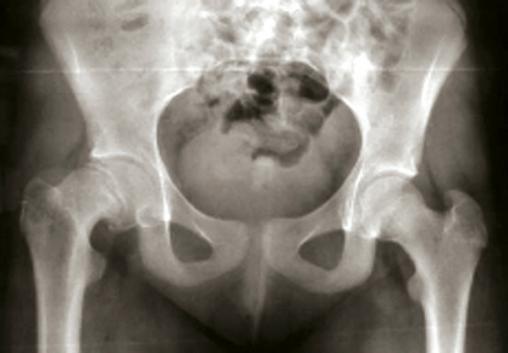

Epiphysiolyse de hanche droite chronique ou stable

L'épiphyse fémorale droite apparaît basculée vers le bas comparée au côté gauche.